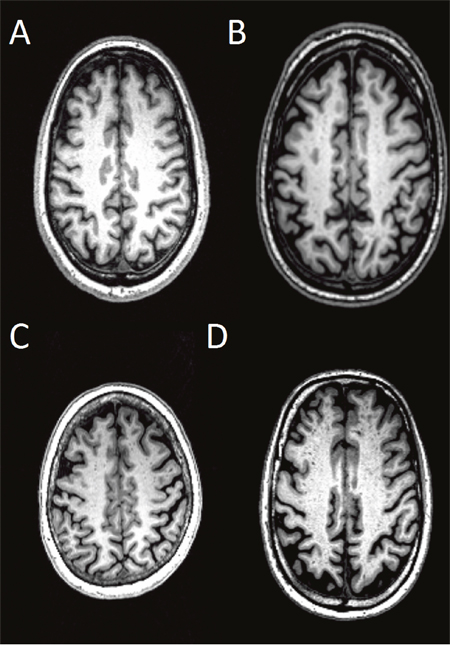

High-resolution 3D MPRAGE T1-weighted structural data was used for the assessment of dPVS [16, 17]. In general, dPVS was defined as CSF-like signal lesions (hypointense on T1 and hyperintense on T2) of round, ovoid, or linear shape with a maximum diameter <3 mm, having smooth delineated contours [1]. The severity is rated based on the number of dPVS, and dPVS in basal ganglia (BG) and cerebral WM are rated separately. The detailed rating are: in basal ganglia, dPVS severity is rated 1 when there were <5 dPVS, rated 2 when there were 5~10 dPVS, rated 3 when there were >10 dPVS but the number is still countable, and rated 4 when the number is uncountable (Figure 3); in cerebral white matter (WM), dPVS severity is rated 1 when there were <10 dPVS in total, rated 2 when there were >10 PVS in total but no more than 10 dPVS in a single section, rated 3 when there were 10~20 dPVS in the section containing the greatest number of dPVS, and rated 4 when there were >20 dPVS in any single section [17] (Figure 4).

Figure 3: Severity scores of dPVS in the BG. Specifically, dPVS severity is rated 1 when there were <5 dPVS (A), rated 2 when there were 5~10 dPVS (B), rated 3 when there were >10 dPVS but the number is still countable (C), and rated 4 when the number is uncountable (D).